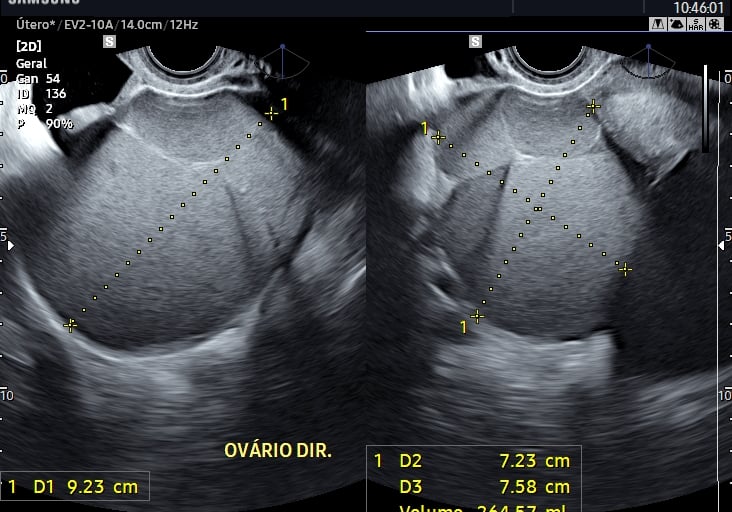

A ultrassonografia pélvica é fundamental para a avaliação do útero, ovários e outras estruturas da pelve feminina. A via transvaginal oferece imagens mais detalhadas e é amplamente utilizada na investigação de patologias ginecológicas.

Avaliação de cistos ovarianos;

Investigação de dor pélvica e endometriose;